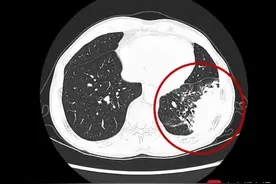

新冠感染后咳嗽不止?医生告诉你这样做新冠病毒感染后,不少人出现了咳嗽、发热、肌肉酸痛等临床症状。部分感染者在转阴后,仍有咳嗽的情况。新冠感染后咳嗽不止,甚至痰中有血丝怎么办?四川大学华西医院呼吸与危重症医学科副主任王刚就相关问题进行了解答。

12月20日,在国务院联防联控机制新闻发布会上,中日友好医院呼吸中心副主任、呼吸与危重症医学科副主任杨汀介绍,不只是新冠病毒感染后会出现咳嗽咳痰的情况,许多呼吸道病毒感染同样如此,感染早期的表现为发烧、鼻塞、流鼻涕,这些症状改善了,但遗留了咳嗽、咳痰的症状,医学上称之为感染后咳嗽或感冒后咳嗽。

21世纪经济报道记者 尤方明 北京报道近期在与多位网友的交流过程中,21世纪经济报道记者发现,不少阳性患者在退烧之后的主要症状是咳嗽,有的是干咳停不下来,有的是浓痰咳不出去。那么,这两种情况分别应该吃什么药来缓解?